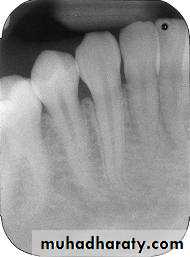

Periapical Examination

Main Indications:Detection of apical lesions.

Assessment of the periodontal status.

After trauma to the teeth and associated alveolar bone.

Assessment of the unerupted teeth.

Assessment of root morphology before extractions.

During endodontics.

Preoperative assessment and postoperative appraisal of apical surgery.

Evaluation of implants postoperatively.

There are two basic techniques for obtaining periapical radiographs:

Bisecting angle technique.Paralleling technique.